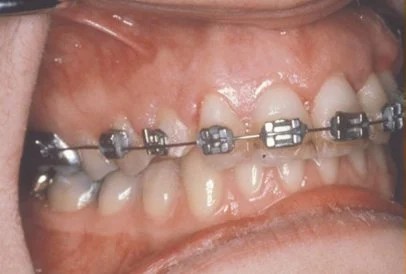

Exposure and bracketing of an impacted cuspid

Impacted canine surgery

The surgery to expose impacted canines takes just about 45 minutes. It is a comfortable procedure that is done under local anesthesia. Mild swelling and soreness may occur for several days following, and can be managed adequately with over the counter pain medicines. During the surgery, the crown of the tooth is uncovered. Depending on the severity of impaction, we may attach a bracket and gold chain to the tooth to “pull” it into place, or we may simply apply a dressing and let it find its own way. It is important to maintain good dental hygiene as part of your home care practice. We will schedule a follow up appointment about a week after surgery to check on your healing.